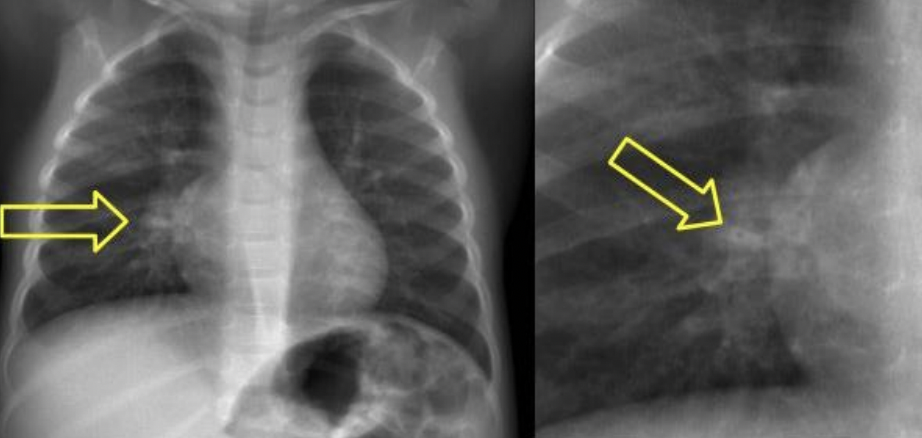

RX ENFISEMA

Aplamaniendo de diafragma: se alcanzan a ver las 12 costillas

Corazón en gota

Hiperinsuflación

Hiperlucidez pulmonar

Disminución de marcas broncovasculares periféricas